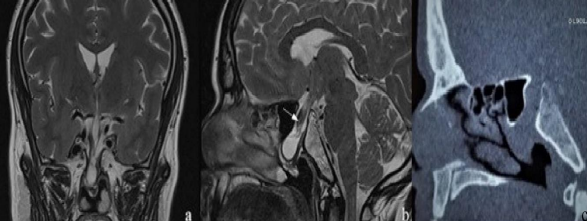

The MRI showed the aspect of transsellar transsphenoidal encephalocele, that protrudes at the level of the floor of the sphenoid sinus. the pituitary stalk had an abnormally thickened aspect herniating through the same sac. A part of the optic chiasm was also included in the malformation. The CT sinus showed the location and the size of the bony defect in the sellar floor. (figure1)

Figure 1: a- coronal section of MRI showing the importance of herniation if the sellar and part of the suprsellar contents .b- on the sagittal section , the abnormal and thickened pituitary stalk is showed by the white arrow .c- the sinus CT showed the bony limits of the defect from the clical recess to the anterior face of the sella.